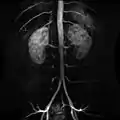

Abdominal aorta

In human anatomy, the abdominal aorta is the largest artery in the abdominal cavity. As part of the aorta, it is a direct continuation of the descending aorta (of the thorax).[1]

Structure

The abdominal aorta begins at the level of the diaphragm, crossing it via the aortic hiatus, technically behind the diaphragm, at the vertebral level of T12.[1] It travels down the posterior wall of the abdomen, anterior to the vertebral column. It thus follows the curvature of the lumbar vertebrae, that is, convex anteriorly. The peak of this convexity is at the level of the third lumbar vertebra (L3). It runs parallel to the inferior vena cava, which is located just to the right of the abdominal aorta, and becomes smaller in diameter as it gives off branches. This is thought to be due to the large size of its principal branches. At the 11th rib, the diameter is 122mm long and 55mm wide and this is because of the constant pressure.[2] The abdominal aorta is clinically divided into 2 segments:

1. The suprarenal abdominal or paravisceral segment, inferior to the diaphragm but superior to the renal arteries.

2. The Infrarenal segment, inferior to the renal arteries and superior to the iliac bifurcation.